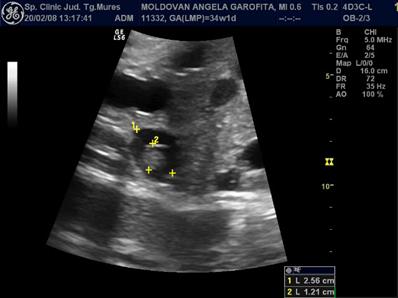

Fig. nr. 271. Formatiune abdominala fetala , la o sarcina de 34 sapt, sex feminin, sugestiva pentru un teratom ovarian.

Fig. nr. 272.

Acelasi fat din figura precedenta, se remarca formatiunea anecogena

intraabdominala, bine delimitata, ce contine o zona ecogena, sugestiva pentru

un teratom. Cu sageata , vezica urinara.